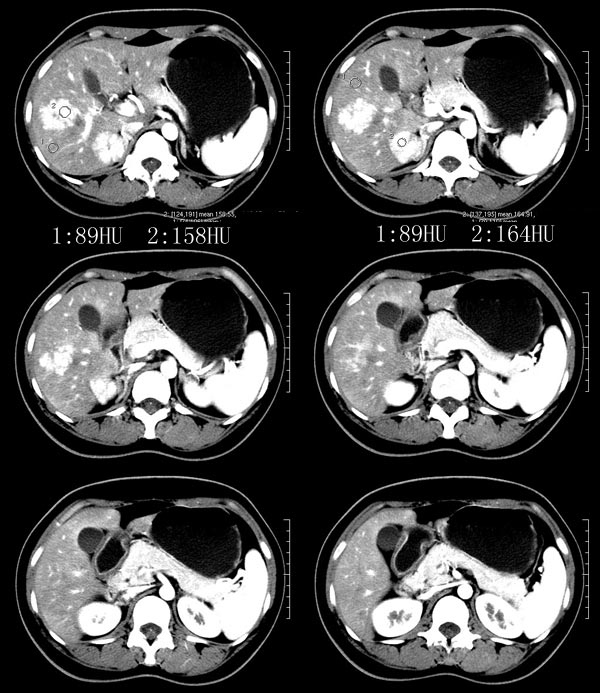

以下是引用52yingxiang在2007-9-16 10:16:00的发言:[br]肝脏局灶性结节增生影象表现(fnh)[br][br]肝脏局灶性结节增生是一种少见的肝脏良性肿瘤,可表现为边界清楚并无包膜的实质性肿块。病变大小不一,多系单发,亦可多发。组织学上是由结构紊乱的肝细胞、库普弗细胞、胆管、血管和粗厚的纤维性间隔所组成。[br]局灶性结节增生的ct表现可归纳为6点:[br]1、密度变化是其特征性改变,平扫多为低密度,少数为等密度,无论增强的早期或晚期均可能呈等密度,增强扫描有助于发现平扫为等密度的病灶;[br]2、中心疤痕,部分病灶在动态ct扫描时早期可看到中心疤痕增生性结节性病灶,ct血管造影也可看到普通ct不能显示的车轮状血管和车轴样改变;[br]3、纤维性分隔影,平扫为低密度,增强后为高密度;[br]4、包膜征象,增强后可以出现包膜强化,晚期较明显;[br]5、邻近血管的改变,主要是肝静脉受压,是发现等密度病变的重要依据;[br]6、瘤内胆管显影,这需要在胆管造影增强的情况下方能显示,出现率不高。[br][br]本例特点: 平扫低密度,增强动脉期明显强化,中心点条状低密度影(考虑纤维瘢痕),静脉期及延时期明显退减并与肝呈等密度,但中心仍可见低密度灶。[br]考虑肝脏局灶性结节增生(fnh)